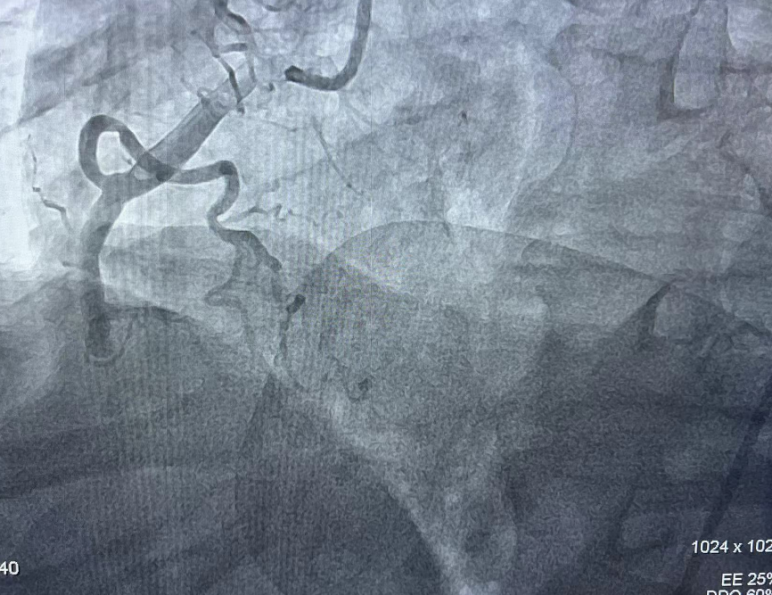

术前造影:右冠脉闭塞

术后造影:右冠脉再通